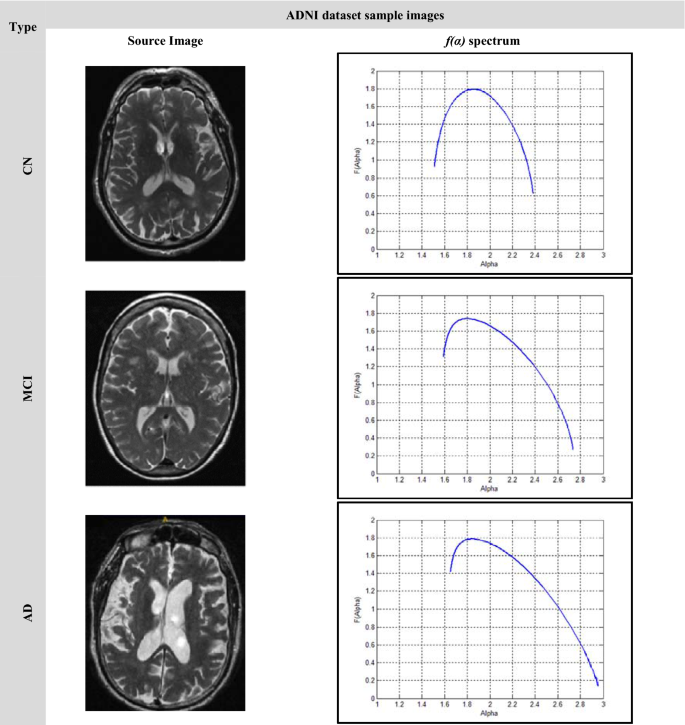

Image samples of a single brain slice for different stages of the used datasets are shown in Fig. 9 and Fig. 10. Figure 9 illustrates the f(α) spectrum for the different stages of AD. According to the progression of the disease with more deposits of beta-amyloid and tau proteins, more amyloid plaques were found causing brain trophy. The more changes in the structure of the brain and its shrinkage, the more the multifractal parameters change, and this is shown by shifting the spectrum to the right and increasing its variability and width. Increasing the difference between the starting and ending values of the singularity spectrum f(αmin) and f(αmax) respectively. Similar behavior can be shown in Fig. 10 with the ADNI dataset. In the CN stage, the singular spectrum tends to be a symmetric and narrow curve for no abnormalities found in the brain structure. While in MCI and AD stages, the spectra lose their symmetric shapes, as well as they, shift to the right with increasing change in the multifractal parameters.

In order to ensure the ability of the multifractal geometry in describing the complex structures for example the changes in the brain structure, a set of comparative spectra representing the different AD stages can be shown in Figs. 11 and 12. As shown in Fig. 11, the singularity spectrum has changed according to the AD stages. The maximum local dimension (αmax) has reached its minimum value in the normal cases with 2.25, while the maximum value has been achieved in moderate cases with 2.8. As the AD disease progresses, the spectrum is broader and shifts to right.